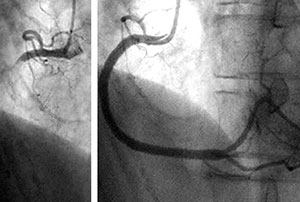

詰まった冠動脈にステントを留置

(左:治療前、右:治療後)

カテーテルを用いた治療(経皮的冠動脈形成術、「PCI」)では、手首や足の付け根に針で穴をあけ、そこから風船のついた細い管を血管内に通して膨らませたり、ステントと呼ばれる細い金網の筒を入れたりして血管の狭いところや詰まったところを再び開通させます。 とくに、治療した部分での細胞の増殖を抑える薬剤を塗った薬剤溶出型ステントを用いた場合の再治療率は5%前後と、良好な成績をあげています。